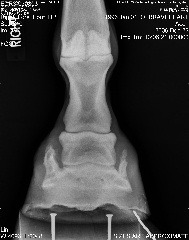

Posted on Sunday, Dec 10, 2006 - 12:49 pm: Left front

|

Posted on Sunday, Dec 10, 2006 - 1:08 pm: Right front

Posted on Sunday, Dec 10, 2006 - 1:12 pm:

| Member: Sunny66 |

Posted on Sunday, Dec 10, 2006 - 1:13 pm: Didn't think I'd be able to get these pics up!! Silly computer.The pics above were taken after the wedges were taken off. |

Posted on Sunday, Dec 10, 2006 - 1:46 pm: Aileen, again take this for what it is worth. In the new pics I think he looks much better. Not weighting his toes so much. |

Posted on Tuesday, Dec 12, 2006 - 6:46 am: Your vet has addressed the questions you posed above Aileen and these feet without the wedges look in better balance than they were back in Nov.DrO |